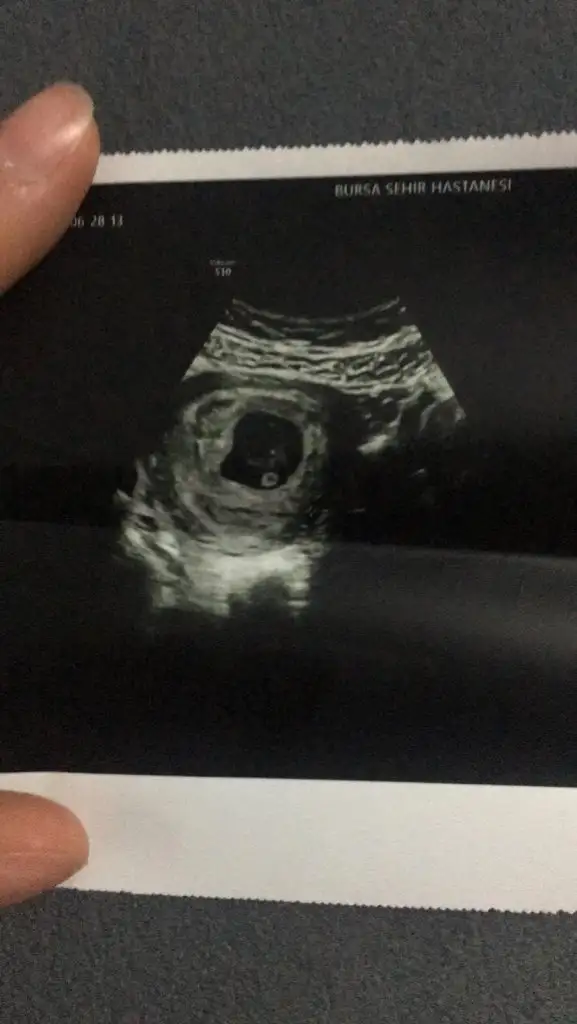

Merhaba 7 buçuk haftalık tahmin ederseniz sevinirim☺️

21,7 KB · Görüntüleme: 67

18,8 KB · Görüntüleme: 74